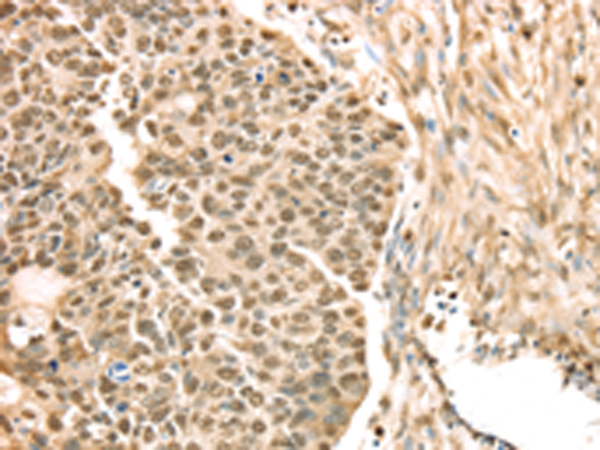

分类: 科研抗体货号: P08719别名: REPA2; RPA32; RP-A p32; RP-A p34应用: WB,IHC反应种属: Human